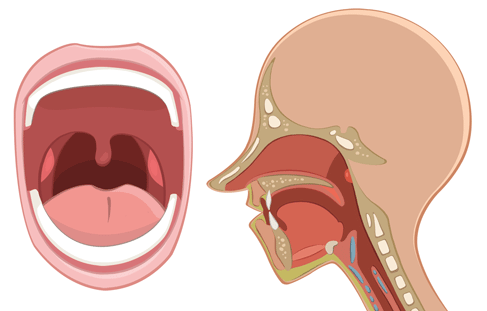

扁桃体炎分急性和慢性

扁桃体炎分急性和慢性,除了咽痛、发热外,有时候还会引起严重的并发征。

急性扁桃体炎:最常见的是喉咙痛,多半全身不舒服、畏寒、发热、四肢疼痛等。有的宝宝还有耳痛及耳闷现象,有些伴有肚子痛、恶心、呕吐,等等。

慢性扁桃体炎:常有咽干、异物感、发痒、刺激性咳嗽、口臭等症状,常有急性发炎史。一部分表现为扁桃体呈不同程度肿大,另外一部分扁桃体纤维化、缩小。

口咽部检查:咽部充血,双侧扁桃体红肿,化脓性扁桃体炎的扁桃体表面可能有脓点,并可连接成片如伪膜状。下颌下淋巴结常肿痛。

口咽部检查:咽部慢性充血,扁桃体大小不定,但是可以看见疤痕和凹凸不平,可能有粘连。患儿常有下颌下淋巴结肿大。